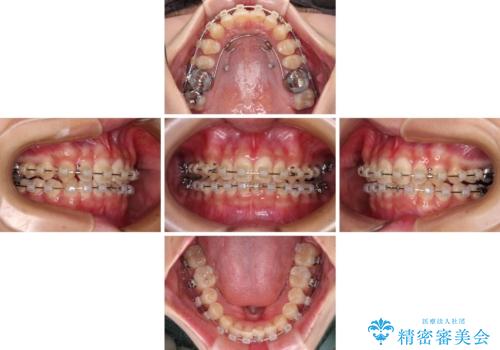

深い咬み合わせとデコボコの歯列をワイヤー矯正で改善

- 前歯のデコボコと深い咬み合わせを改善したいとのことで来院された患者様です。

奥歯の咬み合わせは上顎に対して下顎が後方位にあり、上顎前歯で下顎前歯が隠れるような典型的な過蓋咬合です。

補助装置を用いて上顎大臼歯を後方に移動させながら、ワイヤー装置で歯列を整えて深い咬み合わせを挙上することとしました。

下顎の装置が頻繁に脱落し、治療は難航しましたが、当初予定の2年間で無事に治療を終えることができました。